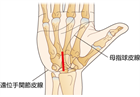

1. 確定診断と鑑別診断のために神経伝導速度検査を行う(推奨度2)

1. 確定診断と鑑別診断のために手根管の超音波検査を行う(推奨度2)